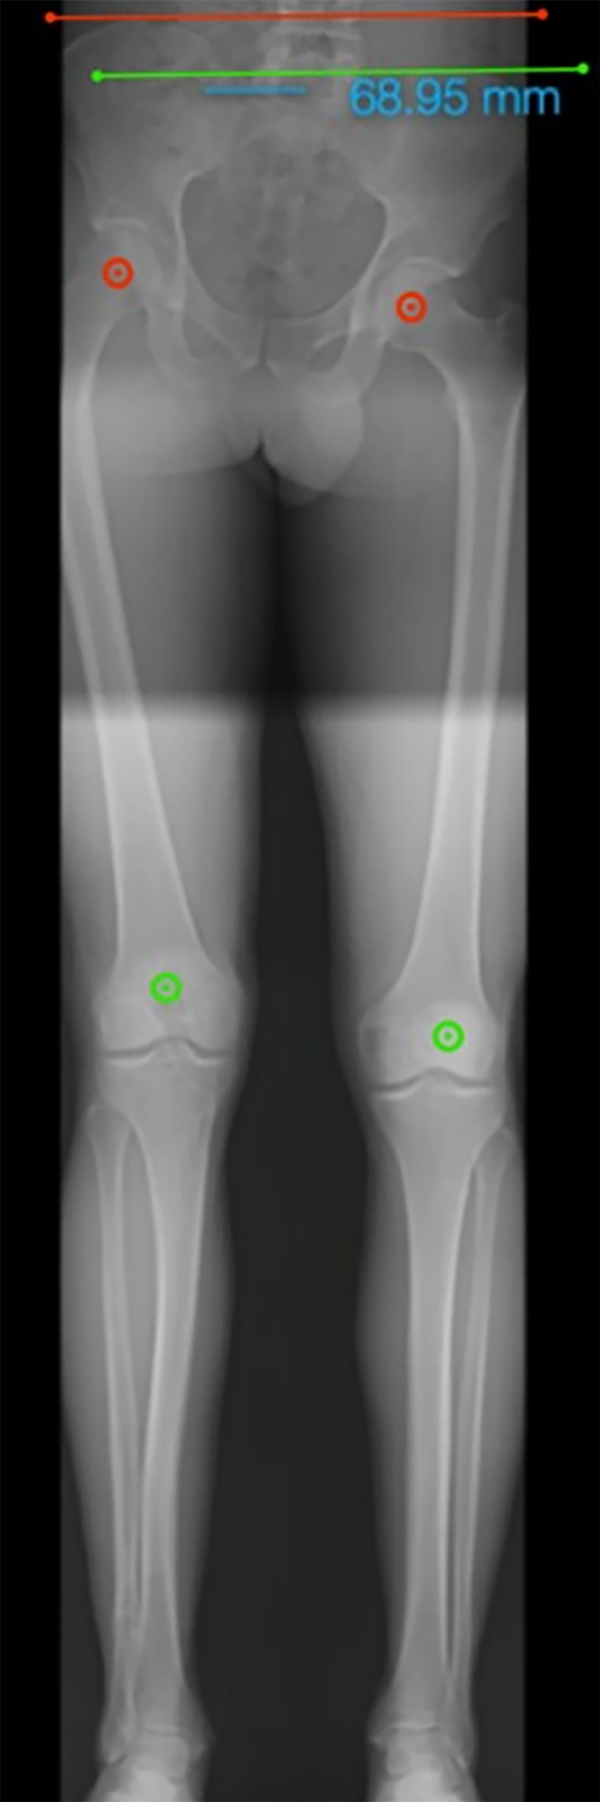

Según Paley,18 la imagen adecuada debe permitir la visualización de la cadera, rodilla y tobillo, con la rótula centrada en los cóndilos femorales, sin embargo, cuando hay un valgo severo, esta referencia se pierde y se debe tomar el eje de flexoextensión de la rodilla. Adicionalmente, la discrepancia de longitud se debe corregir, y la rotación máxima permitida para no alterar los valores es de 5° (figs. 1 y 2).

Figura 2: Radiografía panorámica no adecuada: la línea roja señala la altura del ala ilíaca derecha y en la línea verde el ala ilíaca izquierda, no se corrigió la discrepancia de longitud por el acortamiento del miembro inferior izquierdo; el punto verde señala el centro de la rótula, la cual en la rodilla izquierda no está centrada en los cóndilos femorales.